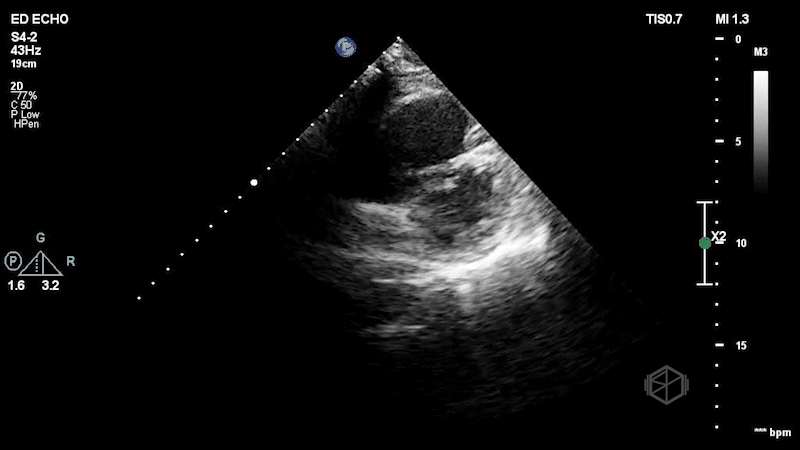

The second SonoProps goes to Dr. Hardeep Singh. Dr. Singh is rotating at Suffolk, demonstrating how POCUS makes a difference in early diagnoses. Dr. Singh evaluated a mid-60-year-old female who presented to the ED with shortness of breath and hypoxia. With multiple differentials to consider, he quickly performed a POCUS that made his diagnosis. The echo clips are shown below:

The patient has a dilated right ventricle obvious even in the parasternal long. The parasternal short view demonstrates a dilated right ventricle with a D-sign that is mostly persistent indicating RV pressure overload. The apical 4 view demonstrates apical hyperkinesis with lateral wall hypokinesis (McConnell’s sign), and the IVC is plethoric with minimal respiratory variation. Dr. Singh previously got a SonoProps for this diagnosis.